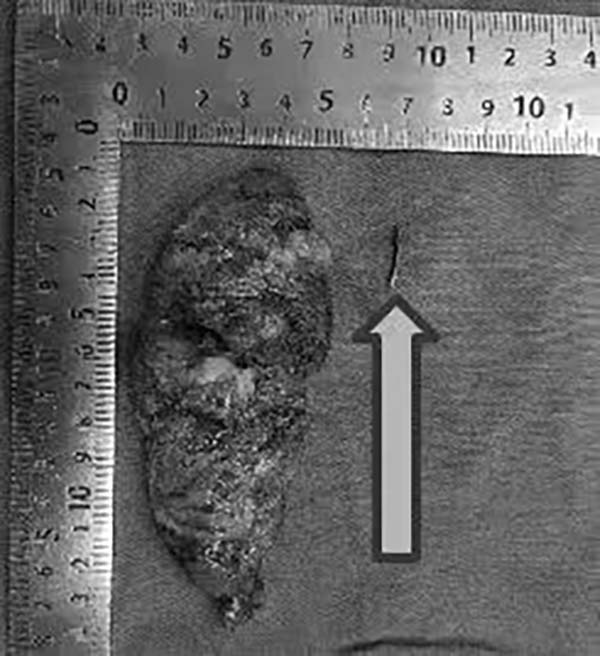

术中探查发现,患者左肺上叶确实存在异物,该异物是导致其长期胸痛的主要原因。手术团队谨慎操作,完整取出异物并对局部组织进行修复。术后病理证实为异物所致慢性炎性改变。

图4箭头处为术中所取异物